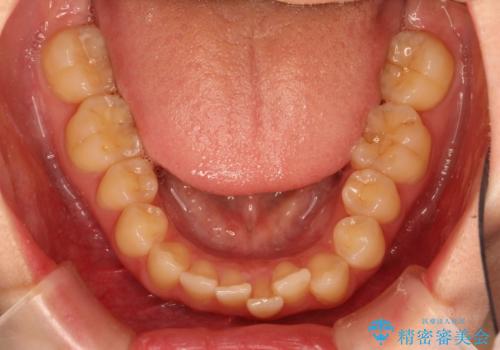

出ている前歯をインビザラインにて引っ込める

- 前歯が少し前に出ているのが気になるとのことで来院されました。

インビザラインにて上顎の歯を全体的に後方に移動させて前歯を引っ込める計画としました。